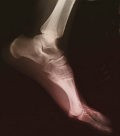

Radiology patient information site launched

The first ever comprehensive patient information site about radiology procedures http://www.insideradiology.com.au has been launched, to help the people for whom a radiology procedure may be a frightening prospect.

The Royal Australian and New Zealand College of Radiologists (RANZCR) has launched the website to give Australians free access to world class, up-to-the-minute, web-based information about radiology tests and procedures in layperson’s language.

There were more than 16 million medical imaging procedures performed in Australia last financial year.

Now all those needing an X-ray, radiology procedure (such as joint injection) or a scan can access information about why their doctor ordered a particular test or treatment, what will happen when they have it, how they need to prepare for it and if there will be any after effects.